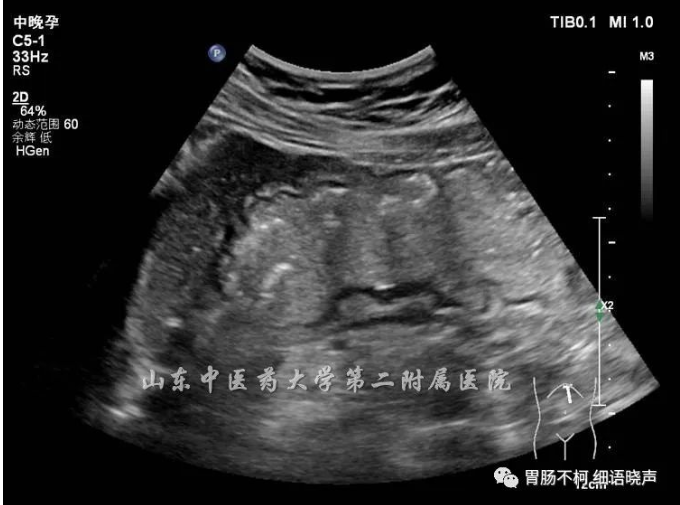

病例二,胃角处胃壁增厚性病变,层次不清晰,回声偏低: